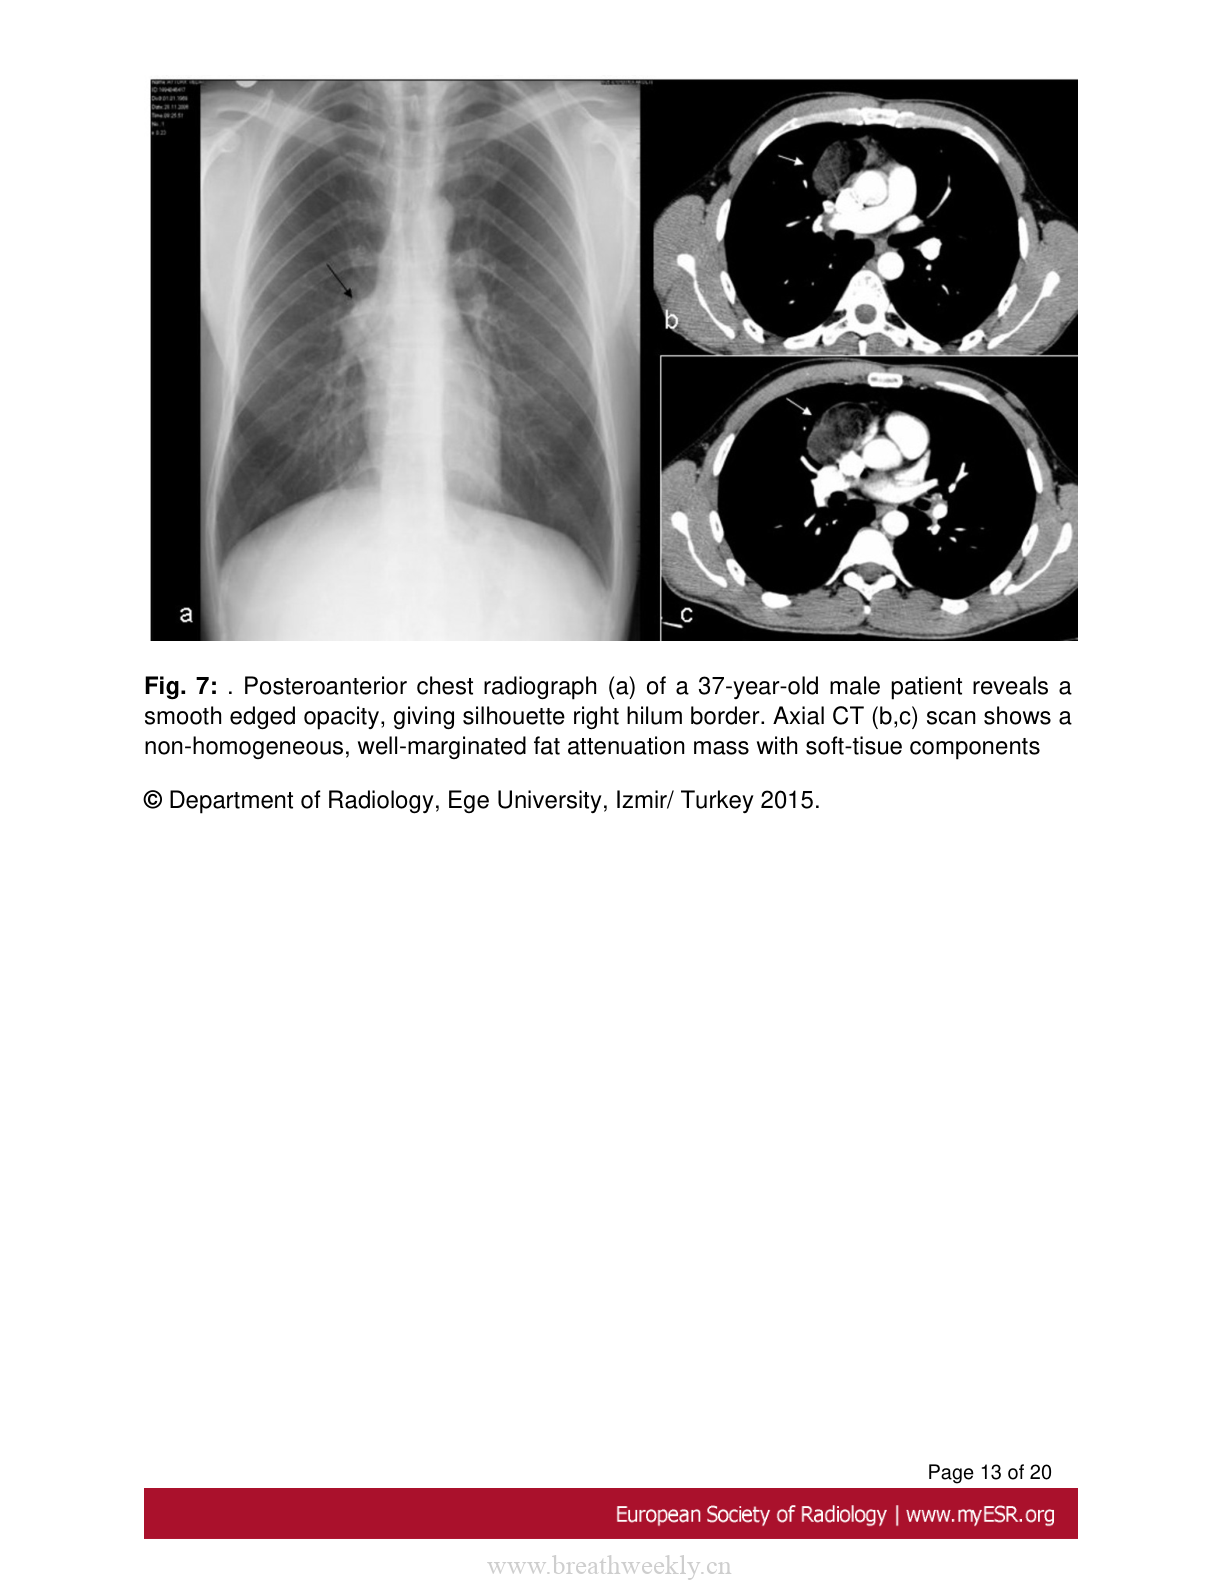

图7:畸胎瘤病例2

37岁男性患者的胸部X线片显示边缘光滑的阴影。CT扫描显示不均匀、边界清晰的脂肪密度肿块伴软组织成分。